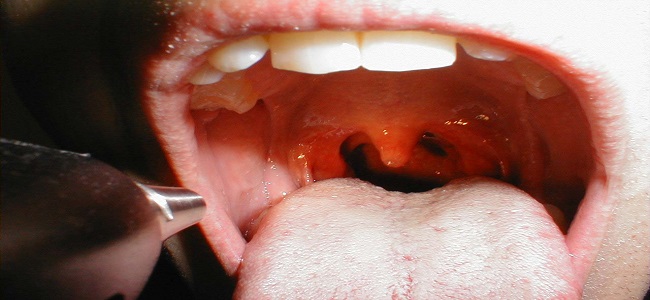

Pierwsze objawy infekcji gardła u małych dzieci mogą nie być charakterystyczne. Dzieje się tak, dlatego, iż często zapalenie gardła jest tylko składową ogólnej infekcji wywołanej przez wirusy. Tak jest na przykład w przeziębieniu. W takiej infekcji wystąpić może: ospałość, niechęć do ssania, niepokój i umiarkowana gorączka. U niektórych dzieci mogą występować wymioty i biegunka. Później zwykle dołączają się objawy ze strony dróg oddechowych: kichanie, katar, kaszel, utrudnione połykanie powodowane bólem gardła. Zaglądając do gardła naszego malucha możemy zaobserwować zaczerwienienie śluzówki i powiększenie migdałków, czasem na podniebieniu mogą wystąpić przebarwienia i pęcherzyki. U niemowląt i młodszych dzieci, które nie potrafią skutecznie odpluwać wydzieliny, może ona zalegać w gardle i krtani, powodując chrapliwy oddech.

Bakteryjne zapalenie gardła u małych dzieci występuje rzadko, szczególnie u niemowląt. Objawy takiej infekcji pojawiają się nagle, są to: wymioty, bole brzuszka, wysoka gorączka, wkrótce pojawia się ból gardła utrudniający przełykanie. Gardło maluszka jest koloru malinowego a migdałki są powiększone z białymi nalotami. Jeśli podejrzewasz, że u twojego dziecka może występować bakteryjne zapalenie gardła, zgłoś się ze swoim maluchem do lekarza. Kolejnym typem zapalenia gardła u niemowląt jest grzybica. Występuje przede wszystkim u dzieci, których układ odpornościowy jest niedojrzały lub funkcjonuje nieprawidłowo. Narażone na infekcje grzybicze gardła są tez dzieci leczone wieloma antybiotykami, lekami przeciwnowotworowymi. Grzybica może mieć postać białych grudek z drobnymi ubytkami w środku, podobnymi do kraterów. Zmiany lokalizują się na tylnej ścianie gardła i migdałkach.